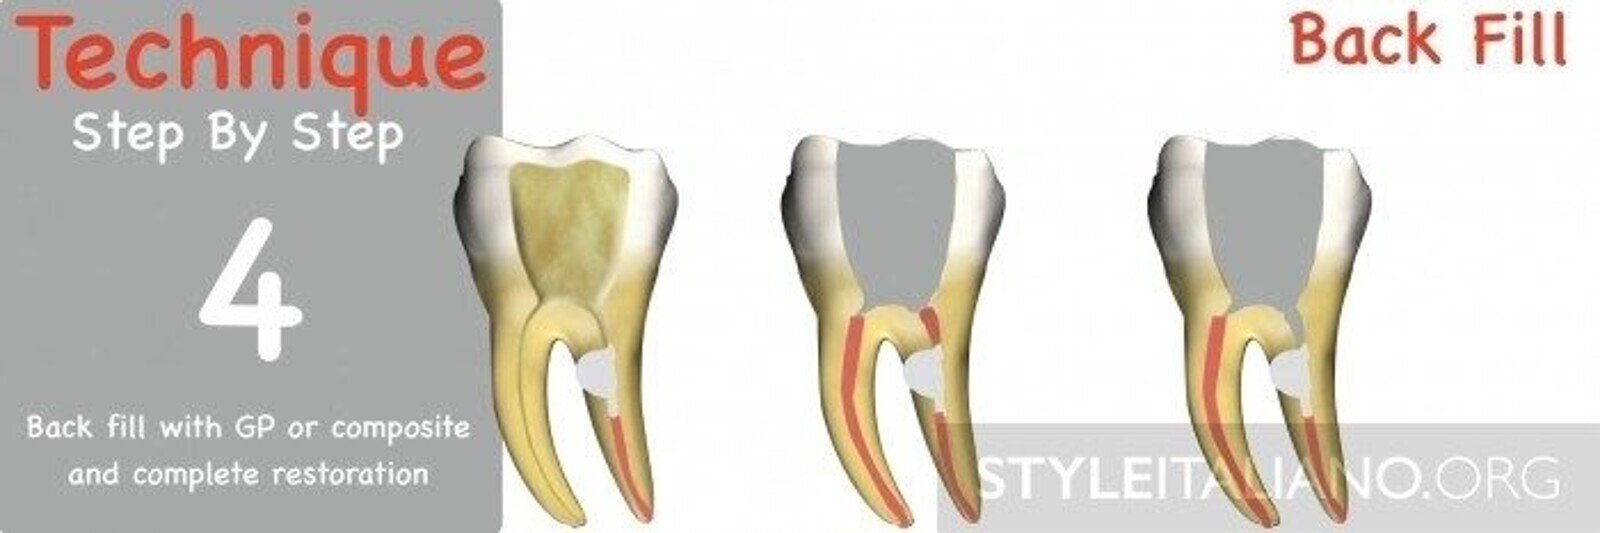

Fig. 5: The last step is represented by backfilling the coronal part with GP or composite material in a second visit.